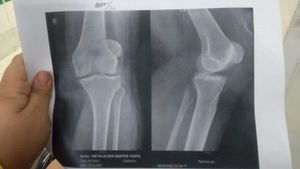

Sofro de uma instabilidade patelar alta grave meus joelhos saem com facilidade do lugar infelizmente preciso de operação mais ate a vaga do sus sair tenho caido com freqüência e viver engessada nao dá. Me ajudem

Me ajudem operar pois exames são caros e eu não  posso trabalhar a maioria do meu dia é ficar deitada para não  cair

Cirurgia do joelhos